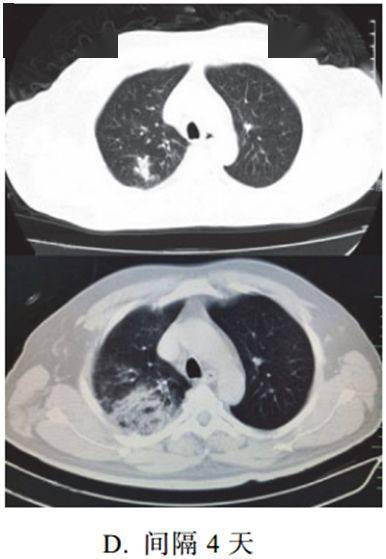

新冠肺炎大多数病例进展迅速,复查 CT 影像发生明显变化

表现为病灶数目明显增多,范围明显扩大,密度增高,病灶分布由外周向中央推进

根据既往 SARS 病理学机制,提示为肺泡腔内聚集大量细胞渗出液、间质内血管扩张渗出;肺泡连通起来形成融合态势(图 2-11)

图 2-11 病灶数目增多、范围扩大 (A-D)